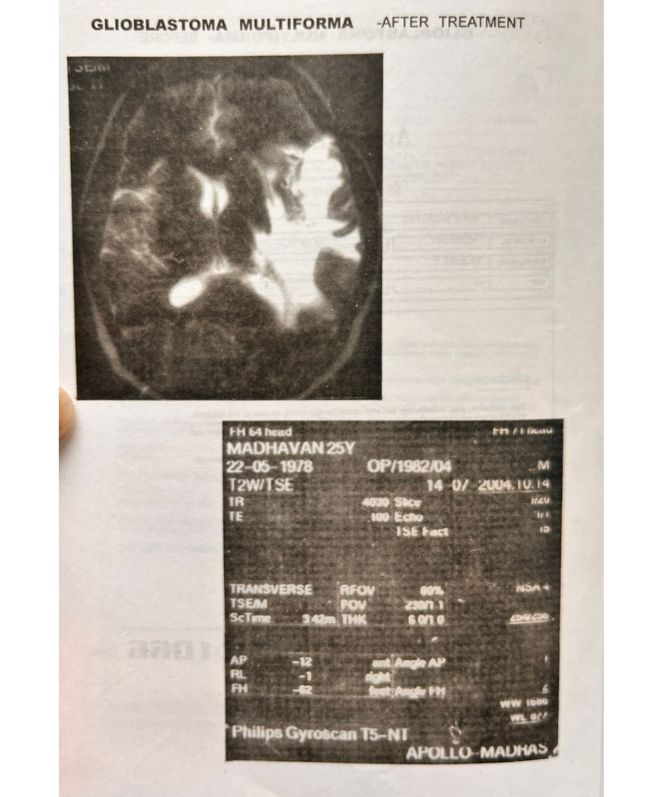

Glioblastoma Multiforma

After - Lung Cancer 1

Glioblastoma Multiforma - Before:

Glioblastoma Multiforma - After: